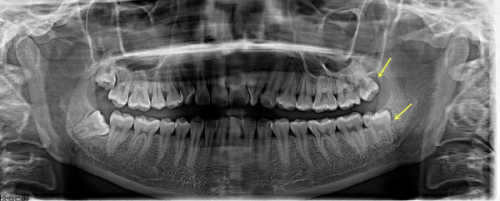

海口平头牙匠口腔医院成立于2021年7月9日,医院位于海南省海口市龙华区金宇街道坡博路1号虹冠大厦第一层106号。占地约500平方米,经过当地监管部门批准,具备合法的医疗许可证。医院营业时间为每日8:00至18:00 。科室设置涵盖了口腔内科、口腔外科、口腔正畸科、口腔修复科等多个专精领域,提供补牙、镶牙、拔牙、牙齿矫正等多项综合口腔服务。同时,配备了精良的医疗设备,如CBCT机、全景机、超声洁治器等,为精细治疗提供了有力保护。